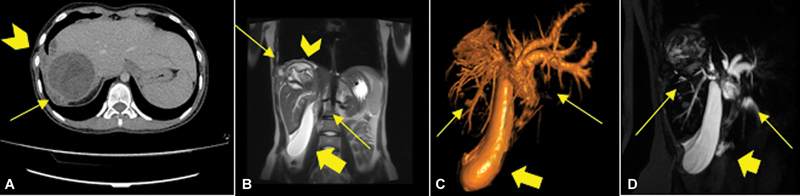

Concurrent rupture of hepatic hydatid cysts into the biliary tree and into the pleural cavity is a very rare complication in echinococcosis and can pose diagnostic and treatment challenges. We present the case of a 15-year-old female patient with recurrent abdominal pain, chest pain, fever, vomiting, jaundice, and cholangitis. Ultrasound, X-rays, computed tomography of the abdomen and thorax and cholangio-magnetic resonance imaging revealed a hepatic hydatid cyst with rupture into the main biliary duct causing obstruction, gallbladder microlithiasis, rupture of the right hemidiaphragm, and pleural hydatidosis. Echinococcus serology tests were positive. Endoscopic retrograde cholangiopancreatography (ERCP) could not resolve the obstructive jaundice. A laparotomy with choledochotomy, removal of hydatid structures, choledochal drainage with Kehr tube, cholecystectomy, Lagrot partial pericystectomy, partial pleural resection, suturing of the diaphragm, and triple drainage (right pleural cavity, cystic cavity, and Douglas pouch) was performed. Perioperative albendazole and antibiotic therapy was administered. The patient had an uneventful postoperative course. Follow-up at 1, 6, 12, and 24 months showed a favorable evolution without relapse of the hydatidosis. The very rare complications of cholangiohydatidosis and concomitant hepatothoracic transit lead to a severe condition, which needs adequate surgical treatment. Clinical presentation and laboratory findings are not specific and may simulate an obstructive jaundice and acute cholangitis of other etiology. ERCP with endoscopic papillotomy offers the advantage of a minimally invasive surgery, but it does not allow a definitive treatment of the whole problem and may be useful as a bridge procedure to drain the bile duct while awaiting definitive surgery.